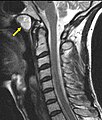

Tornwaldt cyst

Tornwaldt cyst is rare benign head and neck thingy.

• Medial posterior pharyngeal wall.[4]